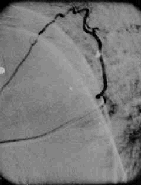

Selective angiography

is a must in every case where active treatment is contemplated.

Dural AVM-angio

Perimedullary

AVM-angio

Glomus type

In the dural AVMs the nidus may be visualized at the

intervertebral foramen. Sluggish clearence of the contrast is a feature

of these lesions.